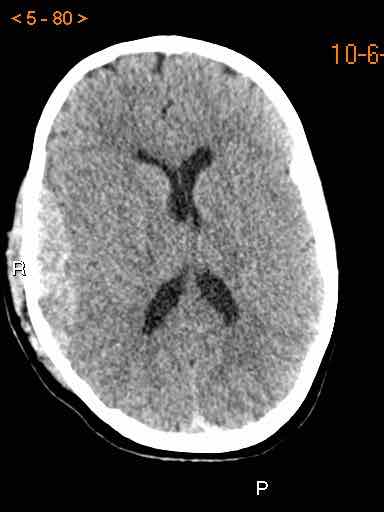

Tụ máu dưới màng cứng đồng tỷ trọng

Khi tụ máu dưới màng cứng tiến triển theo thời gian, tỷ trọng của khối tụ máu sẽ giảm dần và có thể tương đương với tỷ trọng của nhu mô não, khiến việc phát hiện tổn thương trở nên khó khăn.

Đây là trường hợp tụ máu dưới màng cứng đồng tỷ trọng rất khó phát hiện (các mũi tên).

Lưu ý rằng ở mức cắt cao hơn có tụ máu dưới màng cứng hai bên.